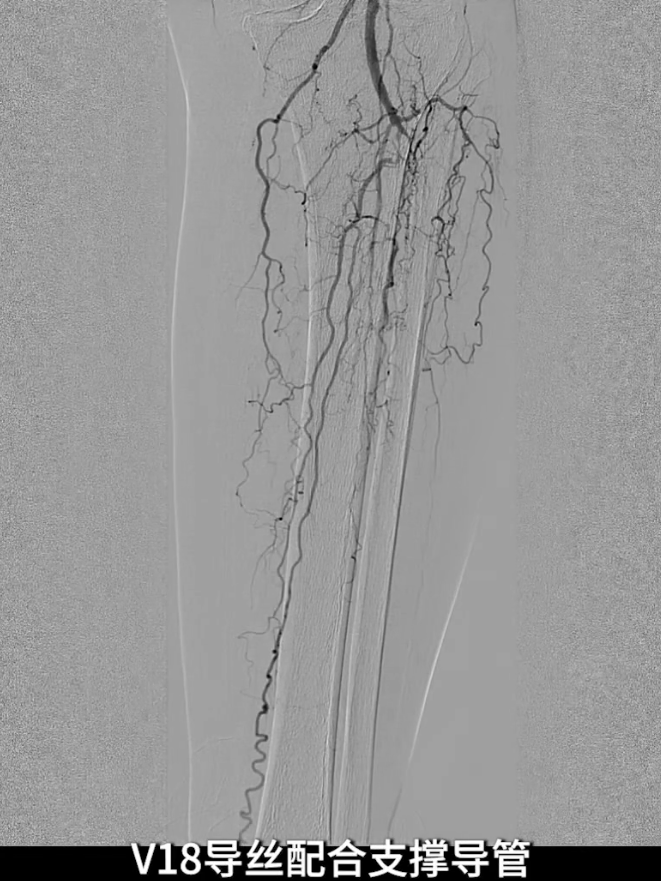

膝下流出道开通

顺行开通尝试:以V18导丝配合支撑导管顺行开通胫腓干,导丝进入内膜下,开通受阻。

逆穿技术应用:改为逆穿胫后动脉远端,支撑导管配合V18导丝经交通支逆行进入腓动脉远端,逐步推送导丝导管通过胫腓干闭塞段,直至腘动脉近端真腔,与近端导管完成对接,建立膝下流出道操作轨道。